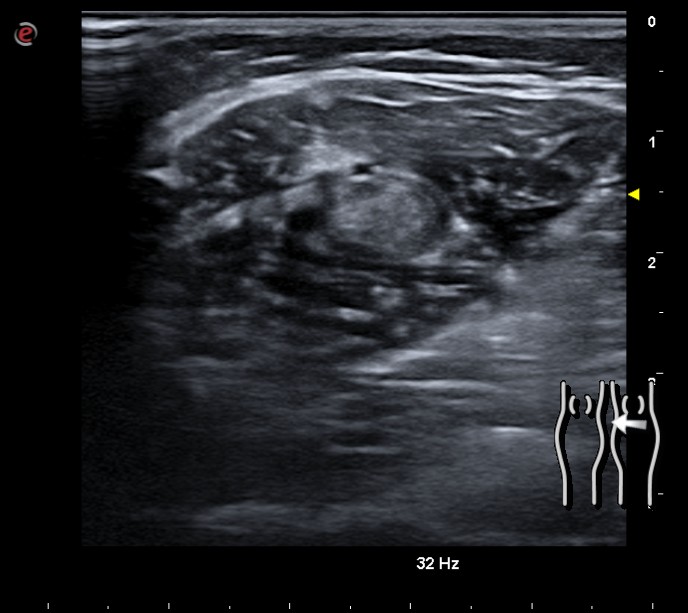

Imagen hiperecogénica en el espesor del gastrocnemio, que se continúa con una estructura anecogénica con doppler a la compresión distal, compatible con trombosis de venas gemelares. El resto del sistema venoso insonado es compresible y con flujo.